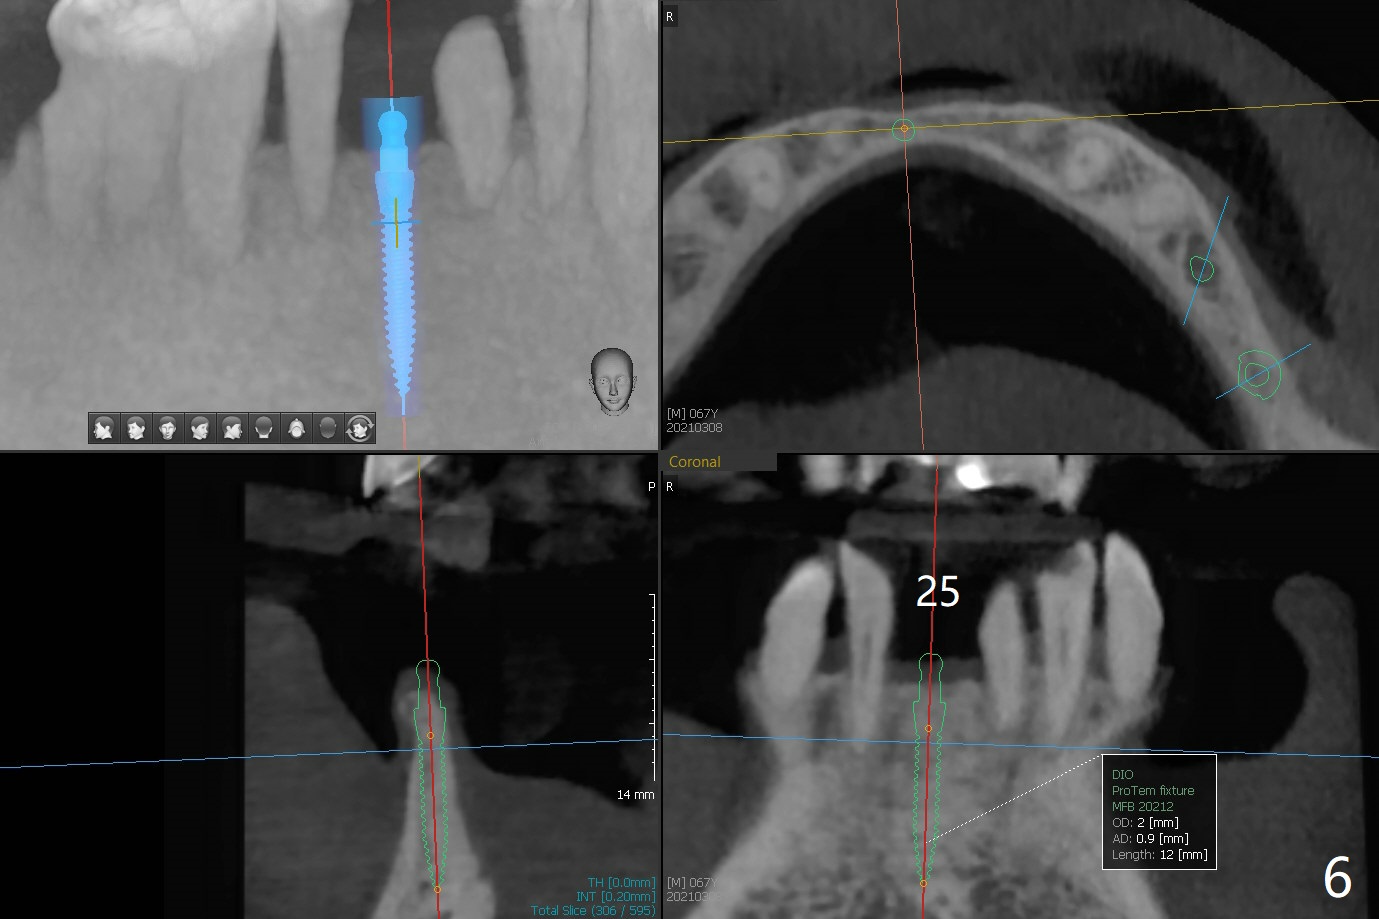

A 67-year-old man requests lower implants (19,20,25) to replace lower RPD with history of food impaction under the partial 5 months post cementation of the upper implants (Fig.1). Due to the atrophic mandible, 1-piece implants will be placed with guide (Fig.2-5) and free hand (Fig.6). Incision will be made at all of the sites for vision and bone graft.